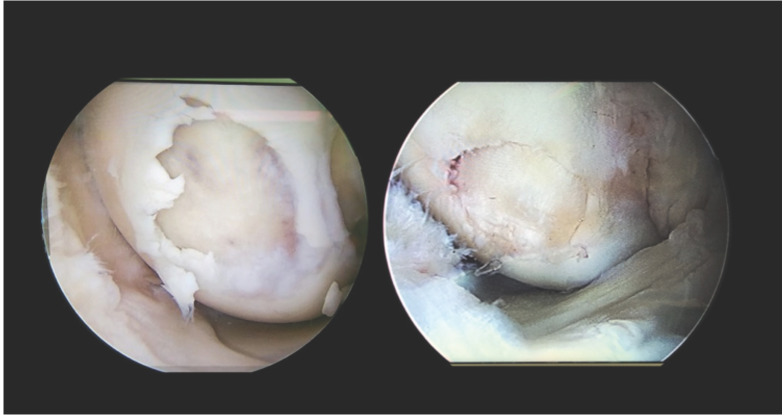

Introduction: Articular cartilage has limited healing potential as it is a hypocellular and avascular structure, hence it is to manage articular cartilage defects. The arthroscopic osteochondral autograft transplantation procedure is minimally invasive and cosmetically acceptable procedure to manage cartilage defects.

Materials and methods: This is a prospective study extending from 2018 to 2023 done at Sports Injury Center, New Delhi involving 36 patients with focal full-thickness chondral/osteochondral defect, age <45 were included. Global Chondral change, Multi ligamentous injuries, varus or valgus malalignment, kissing lesion and defect > 20mm were excluded. The osteochondral lesion was debrided down till healthy cartilage margins, donor graft was harvested from the non-weight-bearing area of the MFC. Lysholm score was used to assess functional outcome.

Conclusion: The OATS procedure is a reliable, reproducible method and its results are encouraging with early mid-term follow-up; however, a long-term follow-up study is required to ascertain the validation of OATS procedure for preventing degenerative arthritis in patients with osteochondral injuries of the knee.